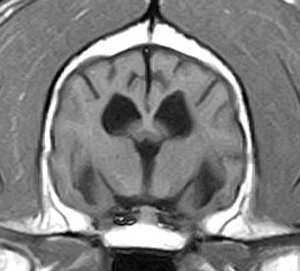

5~6歳以上の去勢手術をしていないオス犬に多い病気ですが、メス犬や去勢した犬に起こることもあります。お尻の筋肉が萎縮した結果、筋肉の隙間から直腸や膀胱が皮膚の下にとびでてしまいます。これにより便が出にくくなったり膀胱炎になったりします。手術をすることで機能回復および今後の致死的な状況を回避することができます。当院では去勢手術→結腸固定→前立腺固定→骨盤隔膜構成筋の縫縮→内閉鎖筋フラップ→浅臀筋フラップの順で通常腹側・臀部左右両側同時に行います。また老化以外に、筋肉が萎縮する原因があったり、腹圧がかかる原因があったりする場合も多いので、再発防止のためそれらの診断・治療も重要です。今回のワンちゃんも無事手術も終わり元気に退院しました。よかったね。